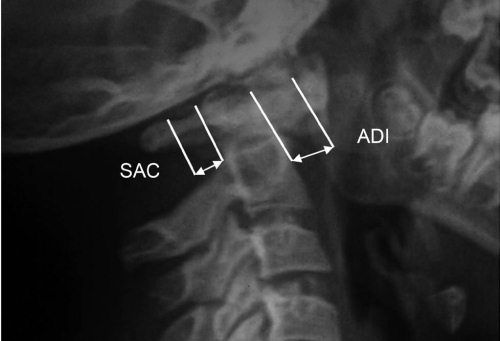

При обнаружении пороков развития с нестабильностью CI–CII или воспалительных процессов в этой области величину SAC необходимо уточнять по КТ, так как она может уменьшаться за счет гипертрофии связок зубовидного отростка. SAC может быть увеличено при пороках за счет spina bifida posterior CI, что является нередкой аномалией, компенсирующей ширину позвоночного канала и не нарушающей стабильности в атланто-аксиальном сочленении.

Необходимо учитывать не только абсолютную величину сустава Крювелье, но и ее увеличение на функциональных рентгенограммах, дельта не более 2 мм. Атланто-аксиальное сочленение не обеспечивает сгибание в шее, и переднезадний люфт в этом суставе должен быть минимален.

Рис. 4.5. Боковая рентгенограмма шейного отдела позвоночника здорового ребенка 8 лет. Широкое переднее атланто-дентальное расстояние – ADI (сустав Крювелье) вариант нормы. Широкое заднее атланто-дентальное расстояние – SAC. ADI + зубовидный отросток < SAC. Правило Still не нарушено

Рис. 4.6. Передний вывих атланта после незначительной травмы у ребенка 9 лет на фоне порока развития позвоночника "зубовидная кость". ADI>SAC. Позвоночный канал резко сужен. ADI + зубовидный отросток занимают резервное пространство для спинного мозга – правило Still нарушено